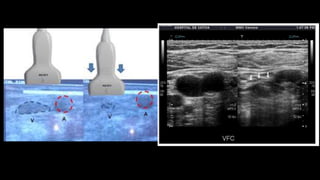

üCompresión transversal (escala de grises o color):

üVFC: Cada 2 cm desde el punto más alto de la VFC hasta canal

aductor.

PROTOCOLO  DE  EXPLORACIÓN üEn  posición  anti-­‐ Trendelenburg  . üInicia  segmento  femoral: üIngle:  Eje  longitudinal  de  la  VIE,  VFC,  VSM  y  la  unión  de  las  VFS  y  VFP. üConfirmar  permeabilidad  VSM  y  FP  (flujo  color) üFlujo  de  la  VFC    (espectral). üEspontáneo,  fásico  y  Valsalva  normal.

üCompresión transversal (escalade grises o color): üVFC: Cada 2 cm desde el punto más alto de la VFC hasta canal aductor. üVFS: A nivel del canal aductor donde se sumerge en los músculos aductores.